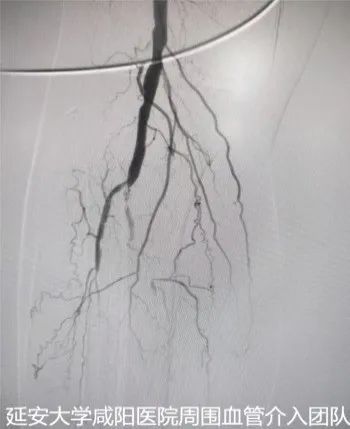

術(shù)前DSA

為了保肢,輾轉(zhuǎn)至我院心血管內(nèi)科一病區(qū),吳棟梁副院長(zhǎng)帶領(lǐng)周圍血管病介入團(tuán)隊(duì)討論、經(jīng)評(píng)估及術(shù)前準(zhǔn)備后于3月24日對(duì)患者進(jìn)行下肢動(dòng)脈球囊擴(kuò)張成形術(shù),術(shù)中下肢動(dòng)脈造影提示膝下脛前、脛后、腓動(dòng)脈動(dòng)脈閉塞,血管鈣化嚴(yán)重及側(cè)支血管形成較差(股腘動(dòng)脈病變TASC II分型為D型);手術(shù)難度較大,手術(shù)失敗患者直接面臨截肢,在規(guī)范化的介入操作下最終開(kāi)通患肢閉塞血管,術(shù)后肢體缺血癥狀立即改善,足背動(dòng)脈搏動(dòng)恢復(fù);下肢變暖了,疼痛消失了,老爺子及家屬終于舒展開(kāi)了愁眉,露出了久違的笑容。